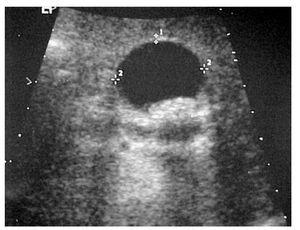

Se realizó un ultrasonido abdominal que informó la presencia de imagen hipoecoica de 15 cm por 10 cm en el cuadrante inferior derecho (Figura 1). El colon por enema reveló enfermedad diverticular con presencia de una imagen esférica adyacente al ciego, con aire en su interior en la etapa inicial del estudio y que fue ocupada por bario posteriormente dando la impresión de estar pediculado con comunicación al ciego, estableciéndose el diagnóstico como divertículo colónico gigante (Figura 2). La tomografía abdominal corroboró el diagnóstico. Se le realizó un ecocardiograma con dobutamina que fue positivo para isquemia aunque la evaluación cardiólogica no contraindicó el procedimiento quirúrgico planeado el cual se llevó a cabo con vigilancia transoperatoria por cardiólogo. Se realizó laparotomía exploradora en donde se encontró divertículo gigante, único, dependiente de colon sigmoides, adherido al mesenterio, colon ascendente e intestino delgado, con el apéndice cecal estrechamente adherido a su pared y con enfermedad diverticular en sigmoides y colon descendente. El divertículo se resecó en su totalidad, en conjunto con el sigmoides y parte distal del colon descendente que tenía la afección descrita y estenosis secundaria (Figura 3). Se complementó el procedimiento con apendicectomía por encontrarse este órgano íntimamente adherido a la pared del divertículo y colecistectomía por colelitiasis. Finalmente se concluyó con una anastomosis colónica término-terminal. Durante el período transoperatorio no hubo complicaciones quirúrgicas ni incidentes cardiovasculares adversos.

¿ Figura 2. Colon por enema.

Steenvoorde7 analizó los estudios de imagen de 135 pacientes con divertículo colónico gigante y encontró que de 104 casos que tenían radiografías de abdomen, en casi todas se observó una estructura de tipo ovoidea conteniendo gas, que se considera característica de divertículo gigante. En 8% de los casos evidenció aire libre o neumomesenterio debido a perforación del divertículo. El diagnóstico definitivo se realizó en su mayoría mediante estudios contrastados como en el caso que presentamos. La tomografía abdominal también fue de utilidad para demostrar el divertículo y evidenció comunicación con el intestino.14 Según Steenvorde,7,15 en 64% de 111 pacientes a los que se practicó colon por enema se demostró la comunicación con el colon pero su uso está contraindicado cuando se sospecha perforación La colonoscopia no ha demostrado gran utilidad para el diagnóstico ya que en la mayoría de los casos el ostium es demasiado pequeño y no permite diferenciar entre una diverticulosis y un divertículo gigante y puede favorecer la perforación.16